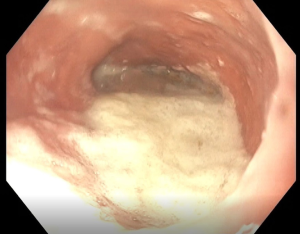

A standardized and validated symptom assessment such as the Eckardt score is useful in evaluation of patients. High resolution esophageal manometry testing should be used for the fine assessment of the esophageal motility, subtypes of the achalasia or characterization of other types of spastic esophageal disorders (Figure 1). The clinical significance of this sub-classification is a subject of debate. A contrast esophagram showing the classic “birds beak” appearance of the narrowed esophagogastric junction and esophageal aperistalsis should be evident (Figure 2A). Patients with spastic achalasia might have a “cork screw” appearance on the esophagogram (Figure 2B). In patients with late or end-stage achalasia, the esophagus may appear significantly dilated, angulated and tortuous alluding to a sigmoidal shape (megaesophagus) (Figure 2C). Megaesophagus has traditionally being approached surgically although it is not an absolute contraindication for POEM, however alternative therapies may be considered due to the increased technical difficulty (11-14). Identification of large amounts of residual food at the initial endoscopy would lead to aborting of POEM procedure to avoid mediastinal contamination (Figure 3).